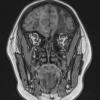

Herpes Simplex type I (HSV-1)

HSV-I Encephalitis (3)